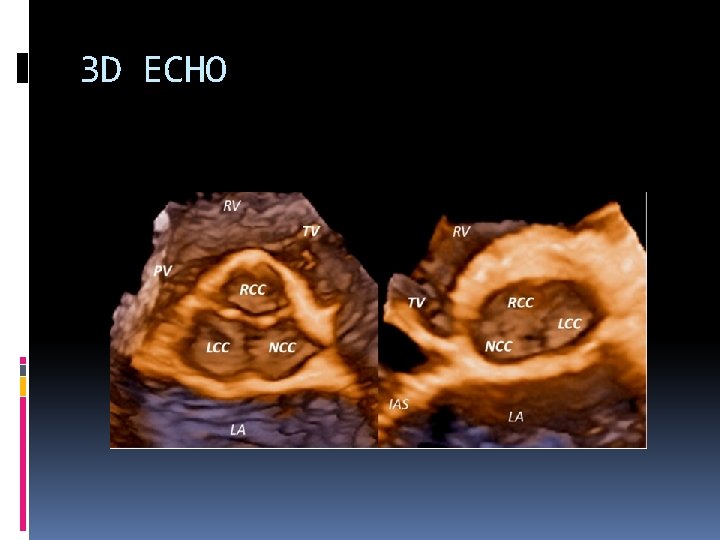

3 D ECHO